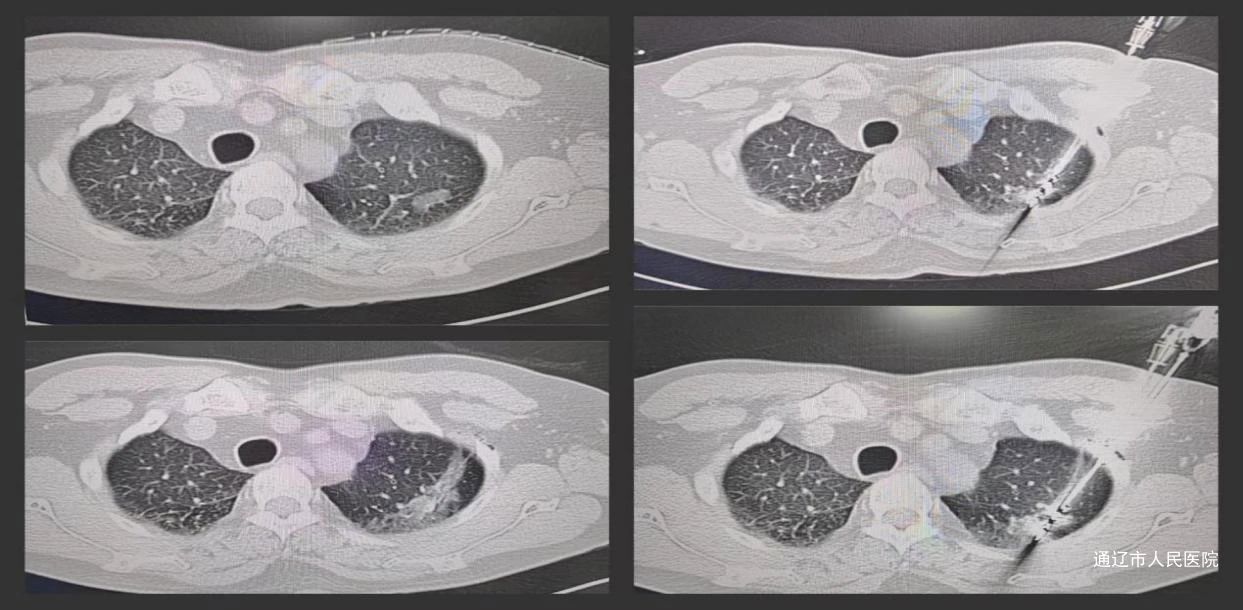

手术在麻醉科刘石磊主任团队全程静脉麻醉及柳晨教授指导下,由CT科阚庆玲医护团队实施肺结节穿刺活检同步微波消融治疗术。术中同时置入微波消融针和同轴穿刺活检针,先给予30w功率,消融30秒,将磨玻璃结节轻度凝固,然后CT引导下沿同轴穿刺针穿刺肺结节活检组织送病理;随后观察微波消融针的位置和深度,调整消融针尖位置,使得消融针尖突破肺结节下缘约5mm,启动微波系统于肺结节消融。消融术毕,即刻CT扫描肺结节呈磨玻璃影改变,肺结节被磨玻璃影完全覆盖,术后病理显示肺浸润性腺。